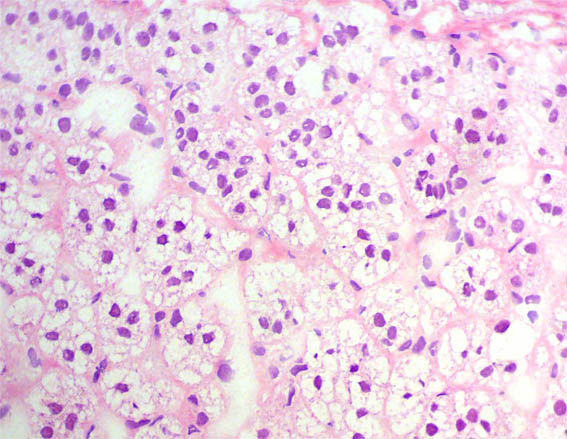

Corte por congelación, H&E, X400.

Figura 5.

H&E, X100.